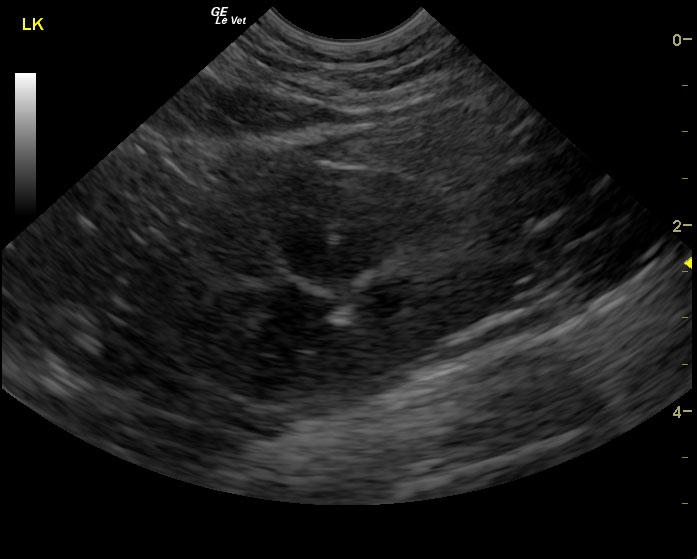

A 6-year-old SF DSH cat was presented for evaluation of chronic cystitis that was non-responsive to antibiotic and Adequan therapy. Both urinalysis and urine culture were within normal limits.

A 6-year-old SF DSH cat was presented for evaluation of chronic cystitis that was non-responsive to antibiotic and Adequan therapy. Both urinalysis and urine culture were within normal limits.